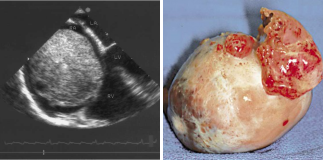

病例二 男,30歲, 右心房占位性病變,心功能Ⅱ級(jí),心律失常,心房纖顫, 平均心室率92次/分。

術(shù)前CT檢查:

右心房增大,其內(nèi)可見(jiàn)占位性病變,通過(guò)獨(dú)有的三維染色后處理,可以對(duì)腫瘤進(jìn)行染色, 以便于確定腫塊與心臟血管及其他周圍結(jié)構(gòu)的關(guān)系。

心臟彩超及食道超聲可見(jiàn)右房?jī)?nèi)囊性占位病變;室間隔及左室壁厚度正常高限;雙房大; 左室收縮功能正常; 彩色血流示: 各瓣膜未見(jiàn)病理性返流。

腫瘤病理結(jié)果與CT檢查顯示的大小、 形態(tài)相符合。

術(shù)后CT檢查:

術(shù)后可見(jiàn)右房形態(tài)正常, 心臟其余各結(jié)構(gòu)未見(jiàn)明顯異常。

640層寬體探測(cè)器CT實(shí)現(xiàn)了3 20排譜黃金寬體探測(cè)器1 6 cm的 超寬覆蓋范圍, 與2 7 ms超 快時(shí) 間 分 辨 率 的 完 美 結(jié) 合 , 可 以 實(shí) 現(xiàn) 微 劑 量 高 清 全 景 電 影 成 像 。 特 別 是 在 冠 脈 檢 查 上 , 可 以 實(shí) 現(xiàn)一次心跳下的心臟冠脈檢查, 實(shí)現(xiàn)復(fù)雜心率情況下高清冠脈成像的100 % 檢查成功率。

此外,強(qiáng)大的后處理功能,能提取心臟冠脈,明確腫瘤大小、形態(tài)、表面特征、位置及三維展示與周圍結(jié)構(gòu)的關(guān)系,還能提供心功能等各項(xiàng)參數(shù),以便臨床對(duì)心臟情況做一個(gè)充分的評(píng)估,術(shù)前充分設(shè)計(jì)好方案尤為重要。